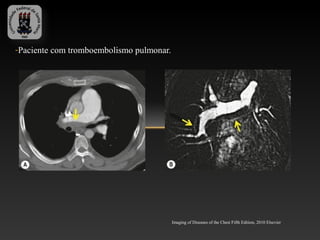

-Paciente com tromboembolismo pulmonar.

Imaging of Diseases of the Chest Fifth Edition, 2010 Elsevier